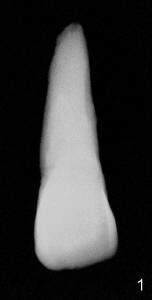

The tooth #8 of a 61-year-old man has obliterated canal probably due to trauma (Fig.1,2 (lateral view)). Initial access shows that the labial portion of the recessed pulpal horn (brown, < in Fig.3 (occlusal view) is not fully exposed, while that the most lingual aspect of the incisal edge (between **) has been removed. Further access appears to be necessary to expose the obliterated pulpal chamber (Fig.7 <) and more of the incisal edge has been violated ( between **). With good exposure, the canal is easily found around the arrowhead (<) in Fig.7. Laterally, the initial file: C6 is straight and slightly labial to the incisal edge (Fig.6). But it is somewhat bent in the front view (Fig.5). After enlargement of the coronal canal with Gates-Glidden files #2 and 3 (Fig.9<), #20 file appears to move distally (<-) and is straighter than the file in Fig.5. Laterally, the #20 file remains without much tension and around the incisal edge (Fig.10). Fig.11 shows occlusal view of the access after application of Gates-Glidden files. Before rotary files, the access is enlarged further both labially and lingually with diamond/carbide endo access burs (Fig.15). Fig.13,14 show 40/.04 file in the canal free without strain. The file seems to move distally further (Fig.13 <-).